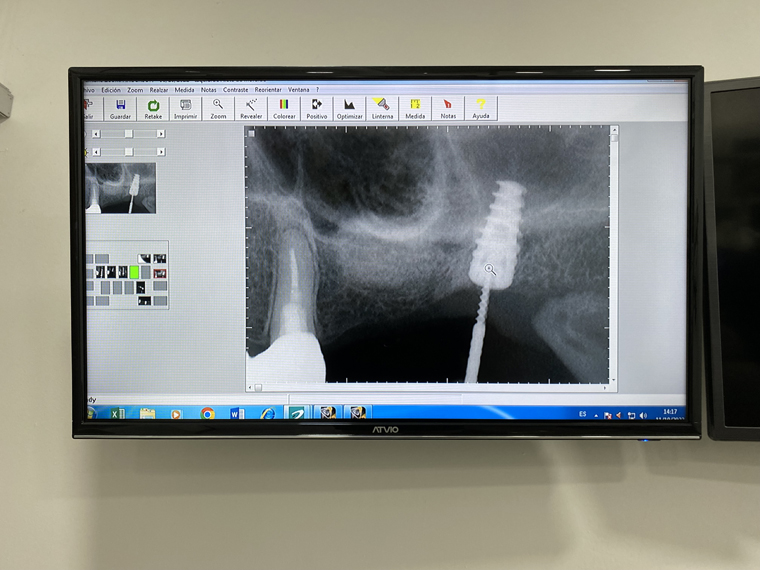

The process started with a 3D scan of her mouth to identify what actually needed to be done. The bone graft was then done followed by the placing of the titanium posts for the implants in her jaw. Great care is taken to make sure that her mouth healed correctly, including three days of infrared laser treatments after each post or graft as well as antibiotics. There is then a wait of several months as the posts set and the jaw heals. Once, her mouth was ready, the next stage involves taking detailed impressions of the mouth with a digital device and actual impressions with a mold. The data from these are used to make the actual teeth at the lab (my crowns and implants were made with the 3D cutter in his office). Finally, the day comes to actually install the implants and bridge. Despite, the length of the process, she was absolutely delighted with the quality of the process, treatment and the results at Dental Studio by Pedro Ortiz.